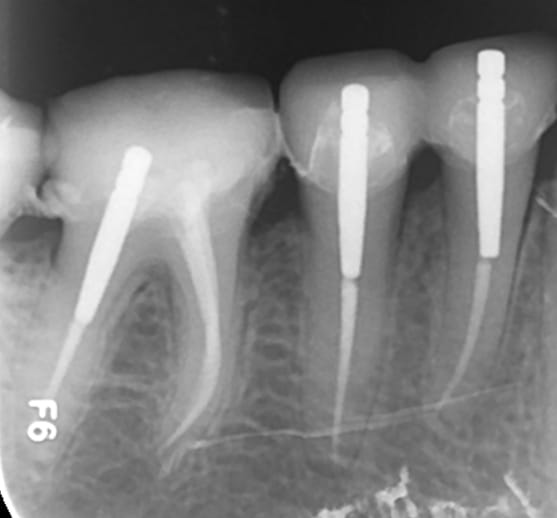

R1 jf6pzt - Eugenol

R2 k7cybs - Eugenol

R3 i3jjn6 - Eugenol

R4 dveqiy - Eugenol

Zoom incisives eb4rim - Eugenol

Retraitement et cour prov ej8sen - Eugenol

Canaux calcifi s e685ou - Eugenol

Avec provisoires o4ho8c - Eugenol

Lol ! je vois qu'on a la meme technique. c'est pas du no post no crown, mais je sais faire ca aussi. ))))))

Sur les monoradiculées, les tenons sont un peu trop courts. Avec les années, si l'os alvéolaire diminue, les risques de fractures de racines augmentent lorsque le bout du tenon se retrouve au niveau du rebord alvéolaire.

Stop à 11 mm pivomatic bleu dans mon cas au delà le pivot calcinable bleu est trop court( après faut passer au vert). Mais ca suffit amplement.

je fait extrêmement peu de tenon, mais tu nous présentes un travail soigné au moins d'un point de vue radiologique, sur la technique endo intrinsèque je laisse le soin a chacun de se faire une opinion